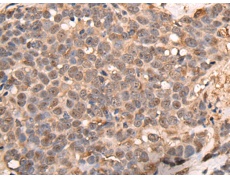

IHC positive control: |

Human thyroid cancer and human tonsil |